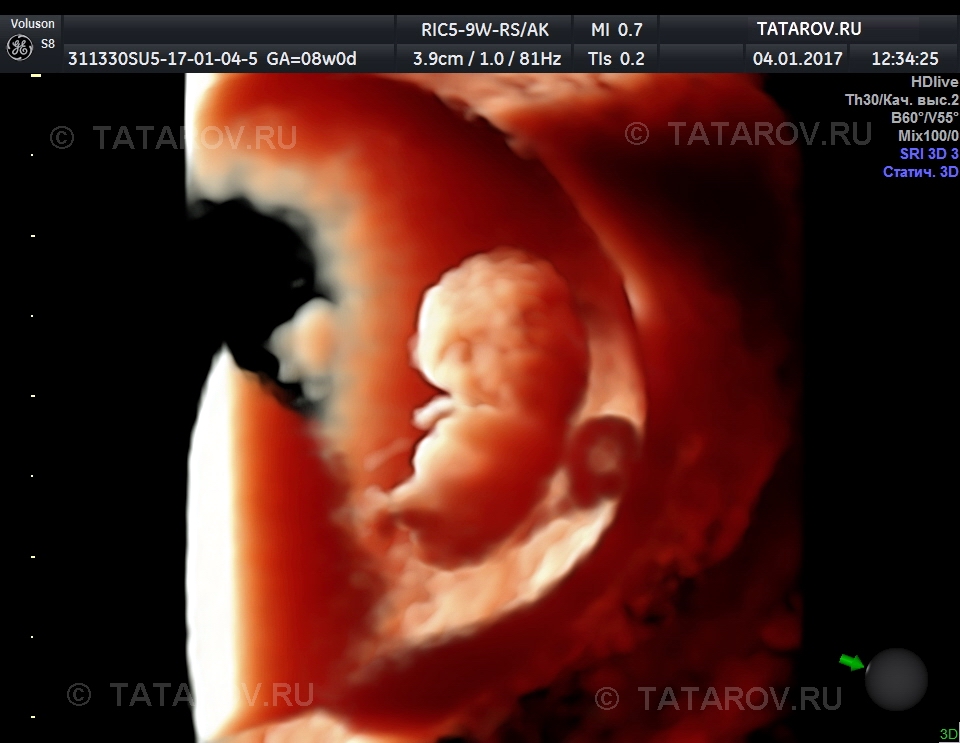

Фотографии на ранних этапах беременности

Раздел: Визуальный дайджест